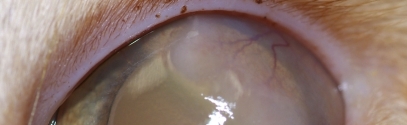

Corneal Diseases in dogs and cats (ed. 1)

This course provides clinically relevant information on corneal diseases of dogs and cats. We will focus on the accurate diagnosis and treatment of a variety of corneal diseases that may be encountered in a general practice setting.